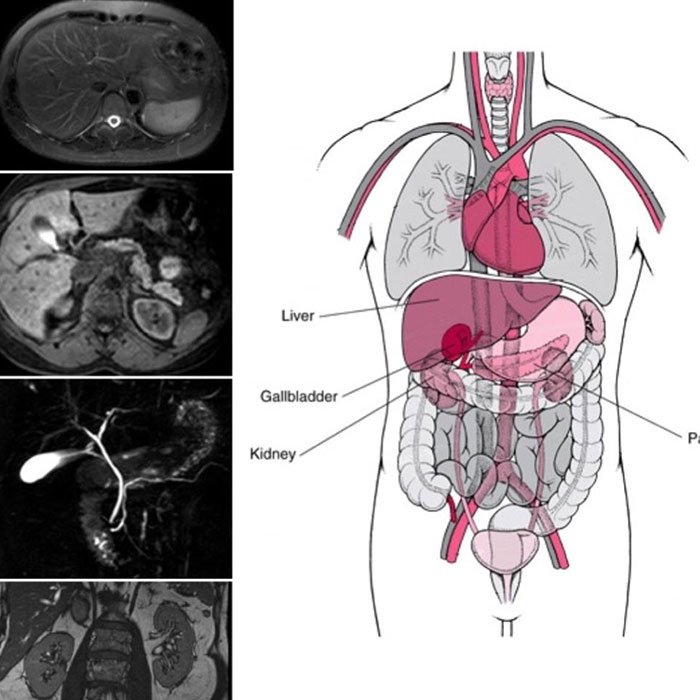

Abdomen radyolojisi halk arasında daha çok karın tomografisi olarak bilinmektedir. Karın bölgesinde yer alan organlara odaklanan bu radyolojik yöntemde, yaşanılan çeşitli rahatsızlıklar için kapsamlı bir şekilde değerlendirme ve analiz yapılmaktadır. Böylece hastaların yaşadığı rahatsızlıklarda daha iyi bir tedavi sunulabilmesi adına destek sağlanmış olmaktadır. Abdomen radyolojisi, radyoloji alanının bir alt bilim dalıdır. Abdomen özellikle bağırsak ve idrar yolu gibi önemli bölgeleri kapsadığından dolayı bu bölgelerde yaşanan rahatsızlıklarda hastaların kapsamlı bir şekilde görüntülenebilmesi adına gelişmiş cihazlardan yardım alınması gerekebilmektedir.

Üst abdomen, karın boşluğunun üst bölgelerinde yer alan karaciğer, safra kesesi, dalak, pankreas, böbrek, böbrek üstü bezleri(sürrenal) ve ana damarları içermektedir. Bu nedenle adlandırmalarda üst abdomen radyolojisi gibi farklı isimler kullanılsa da burada asıl hedeflenen bölgenin daha net bir şekilde belirtilebilmesidir.

Alt abdomen ise karın boşluğunun alt bölgesini ifade eder. Bu doğrultuda mesane, rahim(uterus) ve yumurtalıklar, prostat, idrar kanalı ve seminal veziküller alt abdomen taramaları ile birlikte kontrol edilmektedir.

Abdomen radyolojisinde belirtildiği gibi genel olarak yatak üzerindeki bir cihaz yardımı ile kontrol sağlansa da özel rahatsızlıklarda ya da farklı durumlarda daha değişik tekniklerin uygulanması gerekebilmektedir. Özellikle ultrasonografi en çok tercih edilen yöntemdir. Ancak daha ileri teknikler gerektiğinde farklı görüntüleme yöntemleri de tercih edilebilmektedir. Bu tür durumlarda uzman isteği üzerine abdomen bilgisayarlı tomografisi (BT) ya da abdomen MR’ı çekilebilmektedir. Bu bakımdan başvurulan merkezin yeterliliği ve tıbbi ekipmanlar açısından zenginliği, kişilerin ihtiyaç duyacağı pek çok farklı hizmeti almasını sağlar. Sadece uzman radyologlar tarafından yapılması gereken mevcut işlemlerde, kişilerin en doğru sonuçları ve tedaviyi alabilmesi adına uzman yerleri tercih etmesi gerekmektedir. Bu sayede minimum risk ile en iyi sağlık hizmetinin alınabilmesi ve yaşanılan rahatsızlıklara karşı daha uygun bir çözümün ve tedavinin sunulabilmesi mümkün olmaktadır.